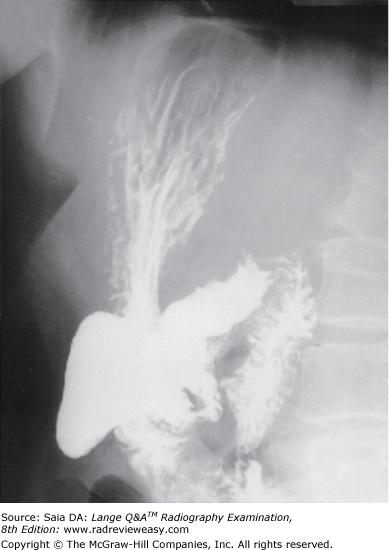

In which of the following positions was the radiograph in Figure A taken?

A RPO

B LPO

C AP axial

D Right lateral decubitus

-The pictured radiograph is an oblique position of the large bowel, illustrating an "open" view of the hepatic/right colic flexure and ascending colon, with the splenic/left colic flexure superimposed on the descending colon. Therefore, the radiograph must have been made in either an RAO (if the patient was prone) or an LPO (if the patient was supine) position. The LAO and RPO positions are used to demonstrate the splenic/left colic flexure and descending colon free of self-superimposition. AP or PA axial is generally used to visualize the rectosigmoid colon.